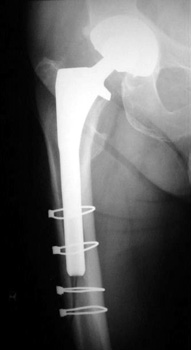

Femoral shaft fracture fixed with cerclage cables.

Control perforation lateral femoral cortex, reduced by cerclage cables. A control perforation of the lateral femoral cortex was performed in this revision total hip replacement to facilitate removal of the old femoral prosthesis. It is reduced by cerclage cables.